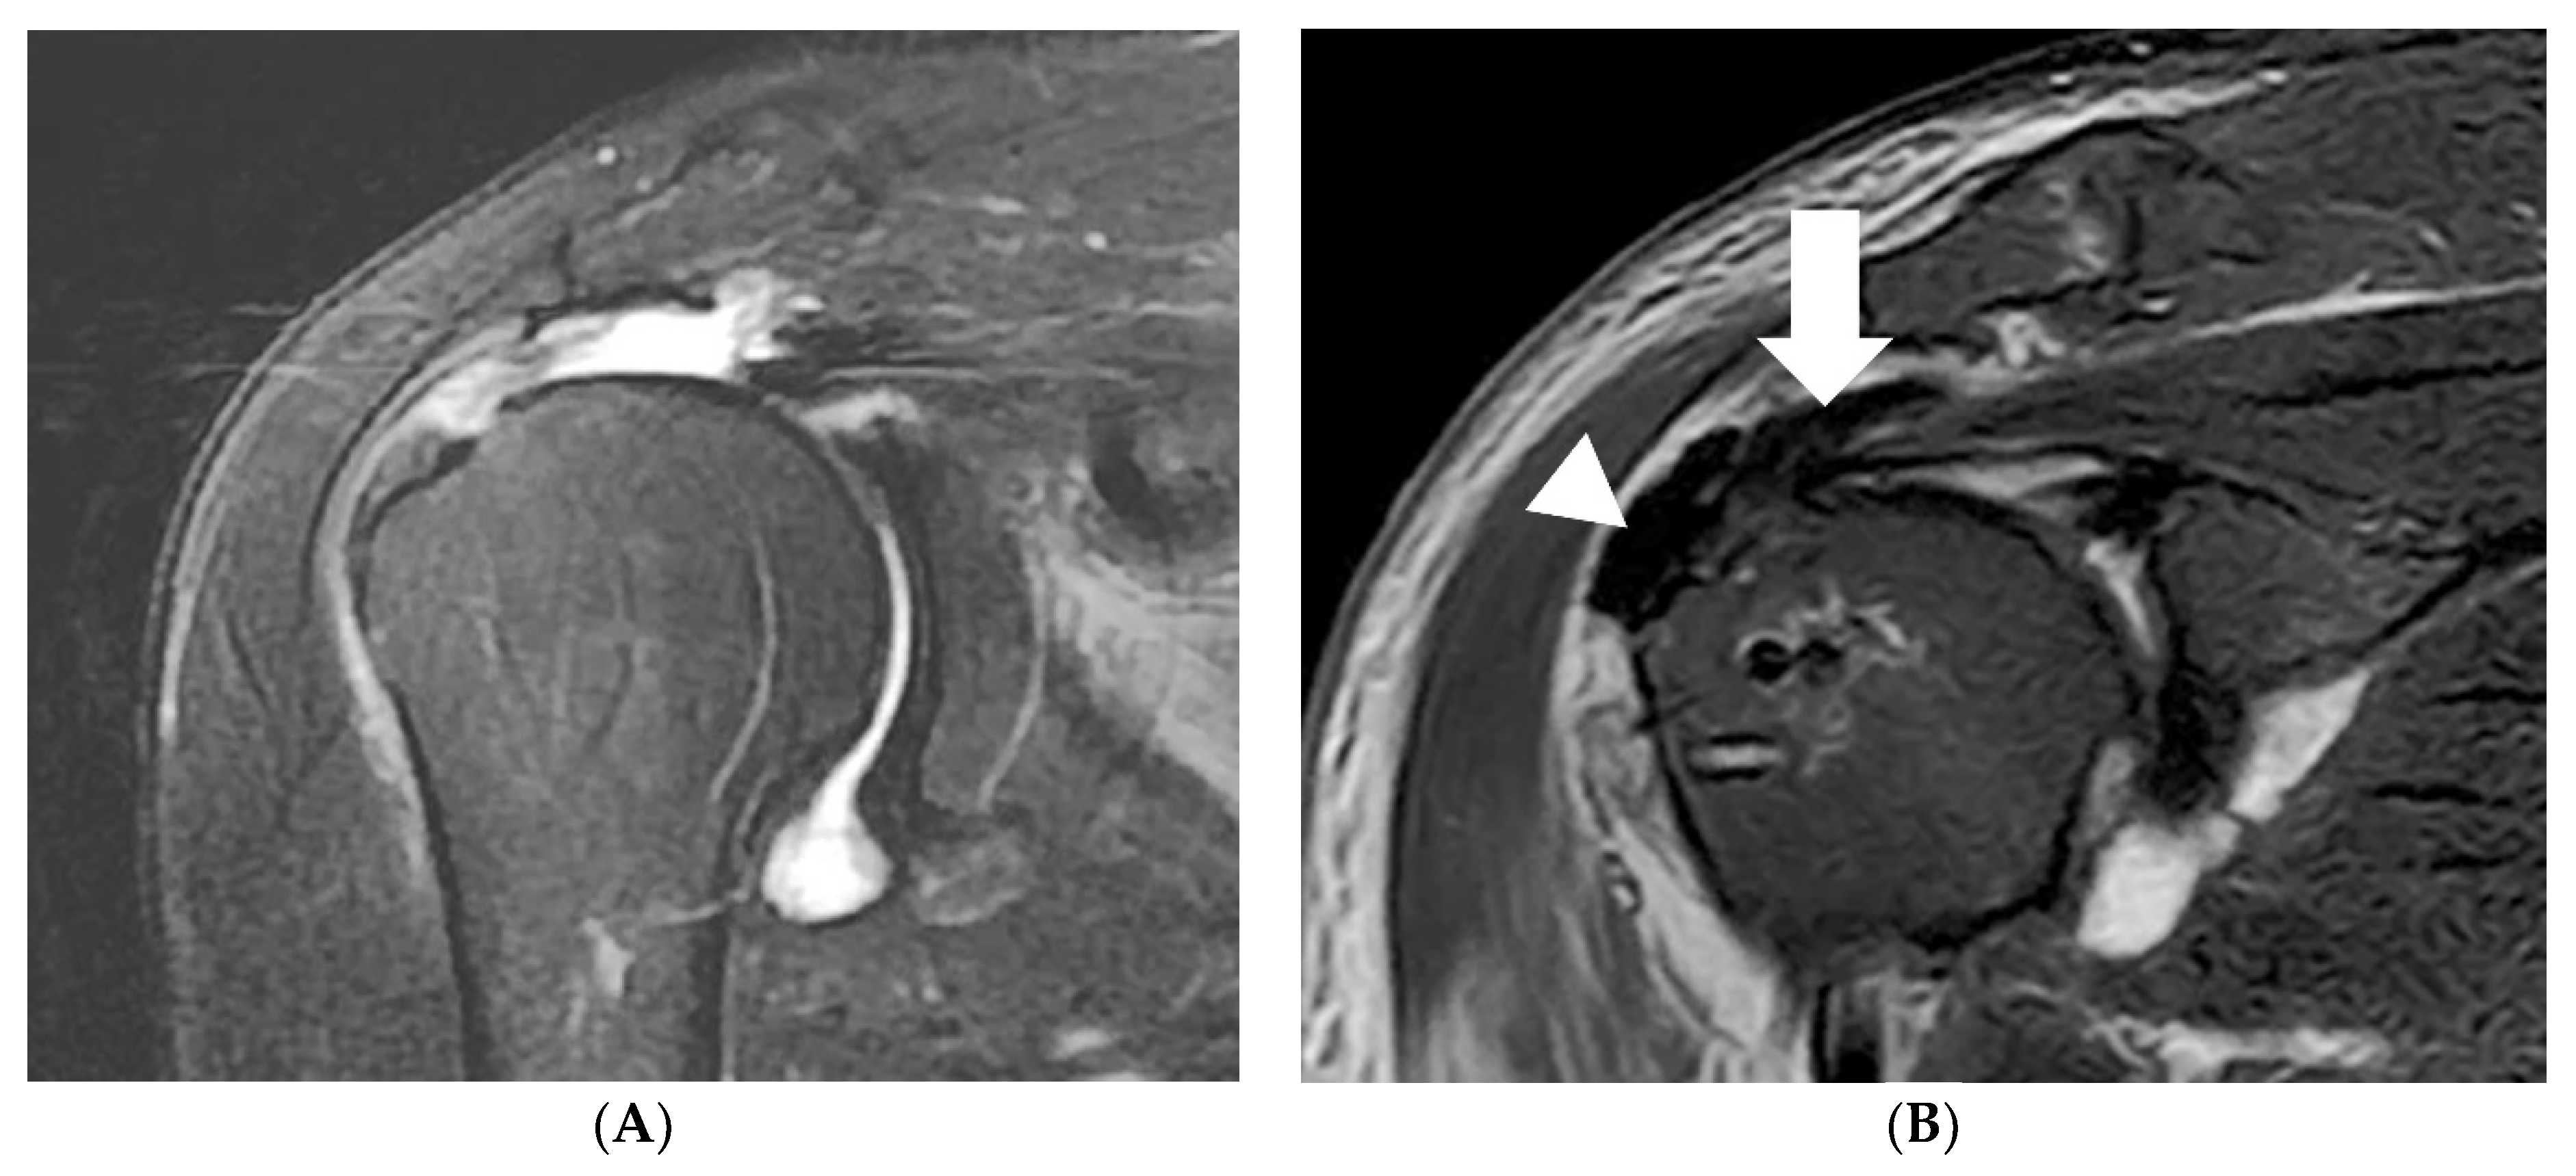

Case

A 71-year-old female patient presented with persistent pain and muscle weakness over several months, leading to a surgical consultation. Preoperative magnetic resonance imaging (MRI) revealed a massive rotator cuff tear. (Figure 3A) Surgical intervention involved medialization rotator cuff partial repair and biologic tuberoplasty using acellular dermal matrix (ADM). Postoperative MRI demonstrated full coverage from the humeral head to the tuberosity (Figure 3B).

Figure 3. (A) On preoperative MRI of a 72-year-old female with a massive rotator cuff tear, findings reveal a large-sized acromial spur and retracted cuff tear. (B) Postoperative MRI shows the medialization and repair of the cuff tendon (arrow), as well as the presence of biologic interpositioning tuberoplasty (arrowhead).